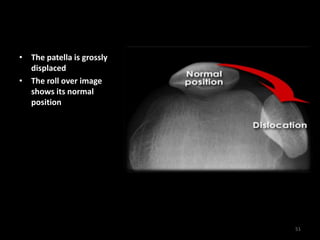

Patellar dislocation - Skyline

• The patella is grossly

displaced

• The roll over image

shows its normal

position